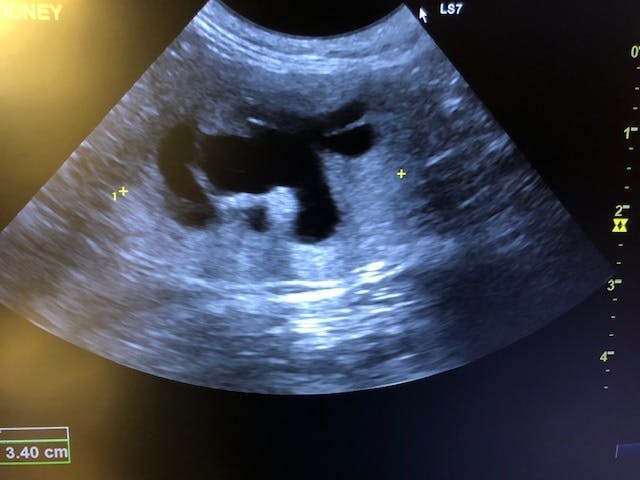

猫は腎臓病になり易いといわれますが、特に高齢の猫はその傾向にあります。

キジ白の「ちび」は、まだ1歳半(推定)。

安全な室内で生活し始めた矢先、ご飯を食べなくなり、病院へ。

末期の腎不全。

腎臓は形をなさず、余命宣告を受けたご夫婦は、最期までお世話して看取る事を覚悟されましたが、